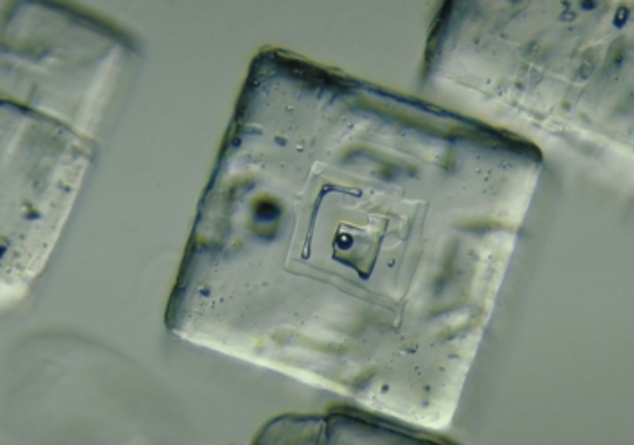

Comparison of crystals in the blood and in the vaccine; on the left, crystalline formations are found in the blood of test subjects vaccinated with Comirnaty (BioNTech/Pfizer), the images on the right show that these types of crystals are also found in Comirnaty vaccines. Image credit: Helen Krenn

In an article from The Expose entitled: Covid Injection Aftermath: Study finds 94% of “Vaccine” Recipients have Pre-Blood Clot Formations and Foreign Particles, by Rhonda Wilson, on 8/24/2022 the author states: An Italian study published two weeks ago in the International Journal of Vaccine Theory, Practice, and Research revealed almost everyone who had been injected had abnormalities after Covid vaXXXination. In 94% of vaXXXinated blood, there was an aggregation of red blood cells and the presence of particles of various shapes and sizes. The study began in March 2021. Using dark-field microscopy, the researchers analyzed blood samples from 1,006 referred to the Giovannini Biodiagnostic Centre for various disorders after being injected with Pfizer/BioNTech or Moderna mRNA vaccines.

In the study, authors noted that the vaccines are purported to contain at least the spike protein from SARS-CoV-2 but are known also to contain foreign particles. “Among those foreign components are metallic objects as demonstrated previously in this journal by Lee et al. (2022) which are confirmed in our results.” Of the 1,006 cases analyzed, only 58 – equal to 5.77% of the total – presented a completely normal hematological picture upon microscopic analysis after the last mRNA injection with either the Moderna or Pfizer vaccine. The blood of 948 – 94% of the study’s participants – showed aggregation of red blood cells and the presence of particles of various shapes and sizes of unclear origin one month after the mRNA injection.

Graphene Ferric oxide crystals (Ferromagnetic Properties) and Trypansoma cruzi parasite eggs were observed in the live capillary blood from a VAXXinated male using Brightfield, pHase contrast microscopy and confirmed with UV absorbance and Fluorescence Spectroscopy, Scanning Electron Microscopy, Transmission Electron Microscopy, Energy Dispersive Spectroscopy, X-ray Diffractometer and Nuclear Magnetic Resonance instruments. – Copyright Hikari Omni Media – Robert O. Young MSc, DSc, PhD, Naturopathic Practitioner – 2021